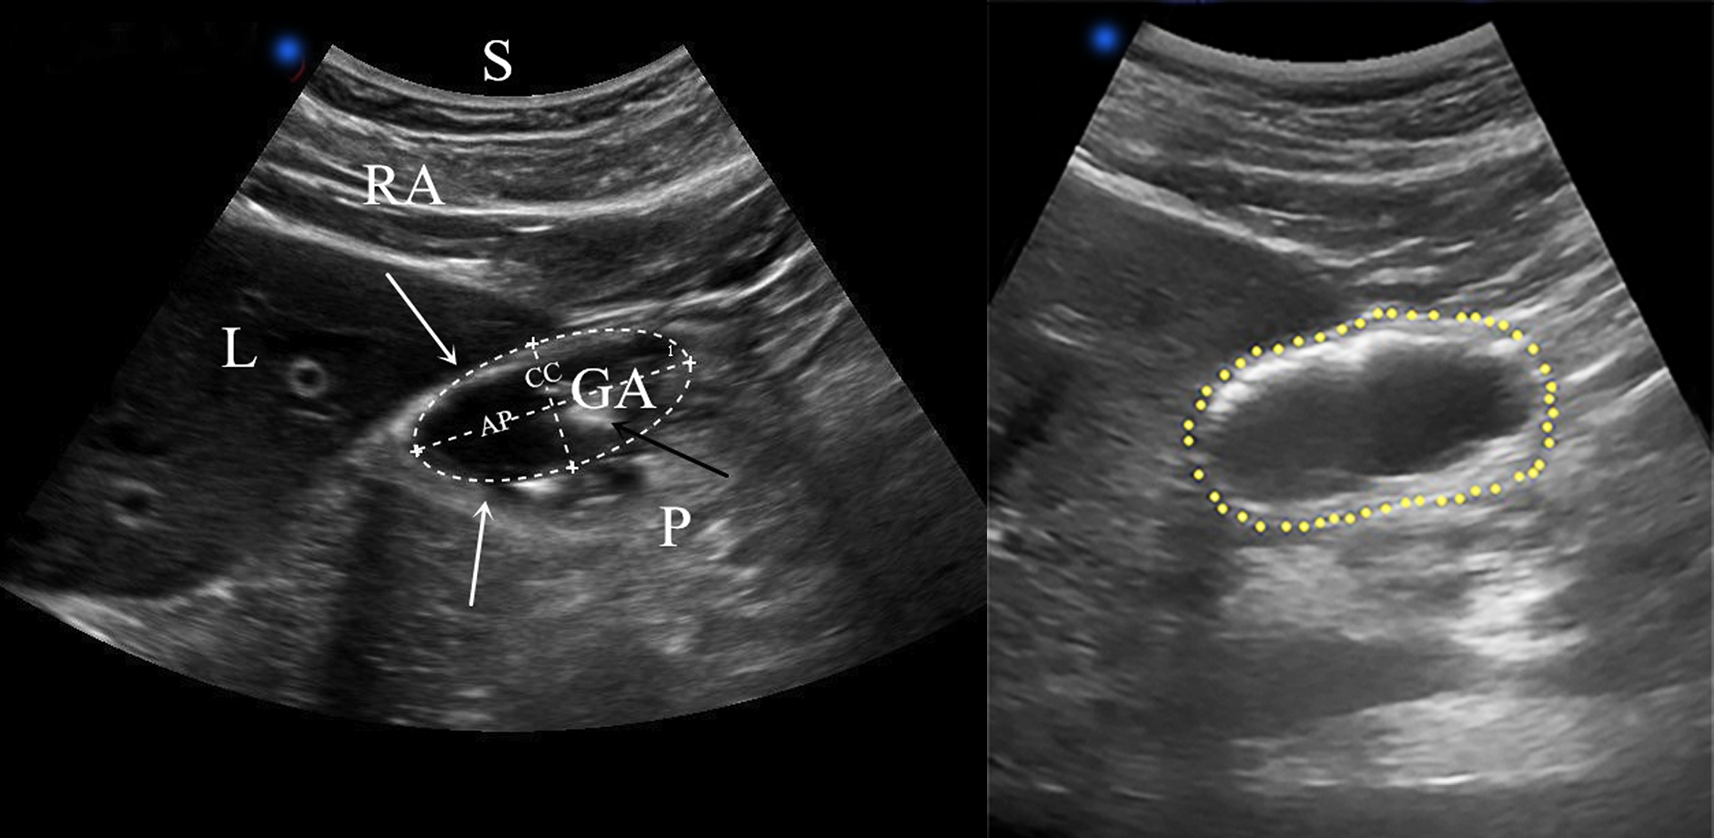

- Is the stomach empty or full ?

- If clear fluid is present in the stomach – calculating the volumen in the stomach

- Does the content in the stomach represent a risk for the patient ?